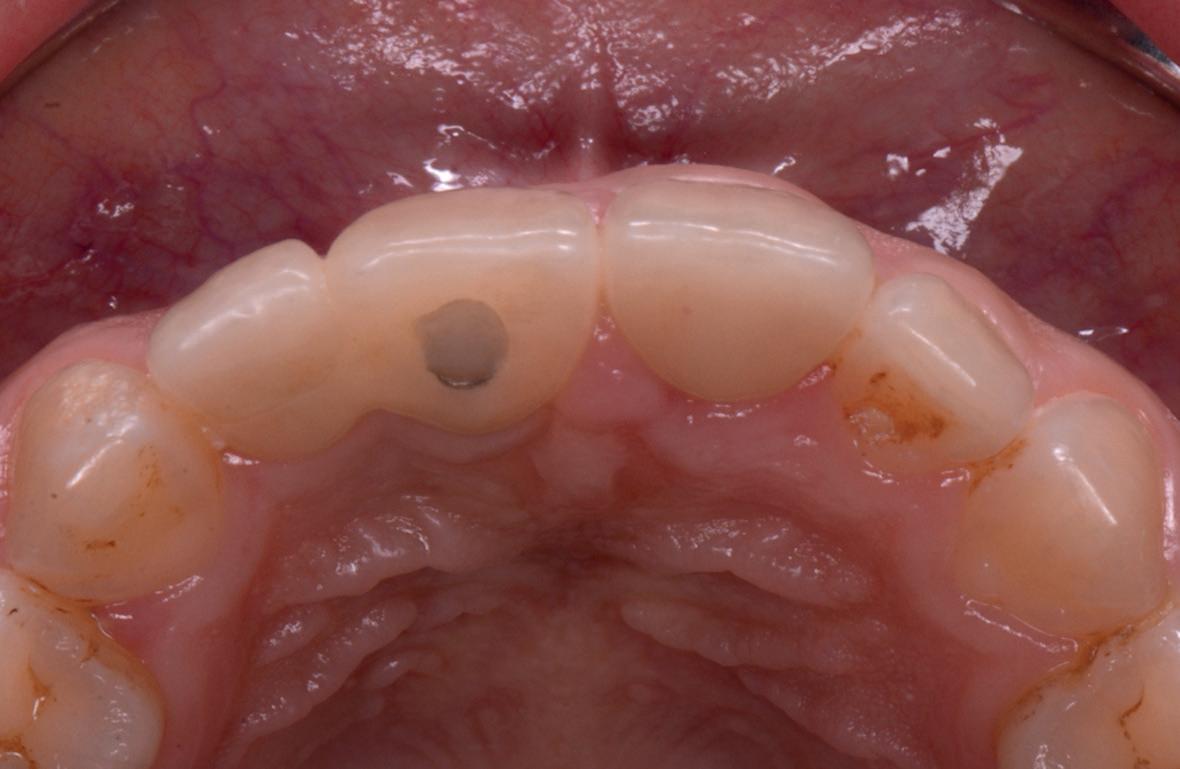

SITE AUGMENTATION Reconstituirea țesutului moale periimplantar și papilar în zona estetică

RECONSTITUIREA țesuturilor moi periimplantare. Scopul acestui raport de caz este de a demonstra procedurile chirurgicale utilizate pentru corectarea unui defect al țesuturilor moi periimplantare folosind țesutul moale interdentar în combinație cu tuberozitatea ca locație donatoare de țesut conjunctiv, utilizând o abordare prin tunelizare într-o zonă estetică.